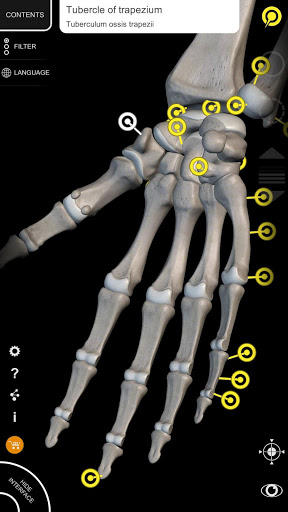

El sistema esquelético completo y algunos otros contenidos están siempre disponibles de forma gratuita, lo que le permite probar la aplicación correctamente.

"Anatomía - Atlas 3D" permite estudiar la anatomía humana de forma fácil e interactiva.

A través de una interfaz sencilla e intuitiva es posible observar cada estructura anatómica desde cualquier ángulo.

Los modelos anatómicos 3D son especialmente detallados y con texturas de hasta una resolución de 4k.

nervioso • Sistema respiratorio • Sistema digestivo • Sistema urogenital (masculino y femenino) • Sistema endocrino • Sistema linfático • Sistema ocular y auditivo CARACTERÍSTICAS • Interfaz sencilla e intuitiva • Rotar y hacer zoom en cada modelo en el espacio 3D • Opción para ocultar o aislar uno o varios modelos seleccionados • Filtro para ocultar o mostrar cada sistema • Función de búsqueda para encontrar fácilmente cada parte anatómica • Función de marcador para guardar vistas personalizadas • Rotación inteligente que mueve el centro de rotación automáticamente • Función de transparencia • Visualización de músculos a través de niveles de capas desde las superficiales hasta las más profundas • Al seleccionar un modelo o un pin, aparece el término anatómico relacionado • Descripción de los músculos: origen, inserción, inervación y acción • Mostrar/ocultar interfaz de usuario (muy útil con pantallas pequeñas) MULTILINGÜE • Los términos anatómicos y la interfaz de usuario están disponibles en 11 idiomas: latín, inglés, francés, alemán, italiano, portugués, turco, ruso, español, Chino, japonés y coreano • Los términos anatómicos se pueden mostrar en dos idiomas simultáneamente REQUISITOS DEL SISTEMA • Android 8.0 o posterior, dispositivos con al menos 3 GB de RAM Reversi